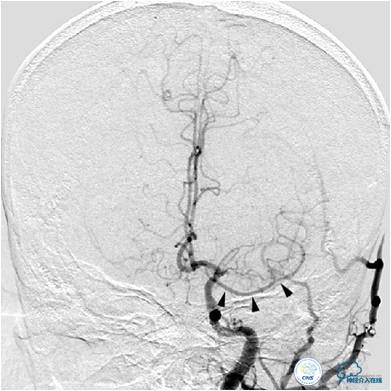

图1:三维造影提示左侧大脑中动脉闭塞,左侧大脑中动脉由一异常血管供血,斟酌为Heubner返动脉。

图3A:左侧颈总动脉造影动脉期,看到异常血管代偿供应左侧大脑中动脉分布区(箭头),双侧大脑前动脉双干显示。

图3B:左侧颈内动脉造影动脉晚期提示双侧大脑半球染色尚可,右侧大脑中动脉供血区由右侧大脑前动脉的软脑膜动脉代偿。

患者入院后,完善颅内CTA(图1)及血管造影(图2~3)检查,发现右侧颈内动脉颅内段闭塞,右侧大脑前动脉依靠左侧颈内动脉系统通过前交通动脉供血,右侧大脑中动脉供血区则依赖于右侧大脑前动脉(ACA)软脑膜代偿供血,左侧大脑中动脉闭塞,依靠一少见血管代偿供血,该血管起自左侧大脑前动脉A2段起始部,代偿供应左侧大脑中动脉供血区。由于该患者灌注CT(图4)未见明显低灌注区,遂给予患者抗血小板、降脂及控制危险因素治疗出院。出院后电话随访未再出现过上述症状。